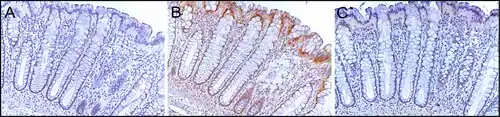

ERCC4 (XPF) in the normal colon

ERCC4 (XPF) is normally expressed at a high level in cell nuclei within the inner surface of the colon (see image, panel C). The inner surface of the colon is lined with simple columnar epithelium with invaginations. The invaginations are called intestinal glands or colon crypts. The colon crypts are shaped like microscopic thick walled test tubes with a central hole down the length of the tube (the crypt lumen). Crypts are about 75 to 110 cells long. DNA repair, involving high expression of ERCC4 (XPF), PMS2 and ERCC1 proteins, appears to be very active in colon crypts in normal, non-neoplastic colon epithelium.

Cells are produced at the crypt base and migrate upward along the crypt axis before being shed into the colonic lumen days later.[32] There are 5 to 6 stem cells at the bases of the crypts.[32] There are about 10 million crypts along the inner surface of the average human colon.[31] If the stem cells at the base of the crypt express ERCC4 (XPF), generally all several thousand cells of the crypt will also express ERCC4 (XPF). This is indicated by the brown color seen by immunostaining of ERCC4 (XPF) in almost all the cells in the crypt in panel C of the image in this section. A similar expression of PMS2 and ERCC1 occurs in the thousands of cells in each normal colonic crypt.

The tissue section in the image shown here was also counterstained with hematoxylin to stain DNA in nuclei a blue-gray color. Nuclei of cells in the lamina propria, cells which are below and surround the epithelial crypts, largely show hematoxylin blue-gray color and have little expression of PMS2, ERCC1 or ERCC4 (XPF). In addition, cells at the very tops of the crypts stained for PMS2 (panel A) or ERCC4 (XPF) (panel C) have low levels of these DNA repair proteins, so that such cells show the blue-gray DNA stain as well.[31]